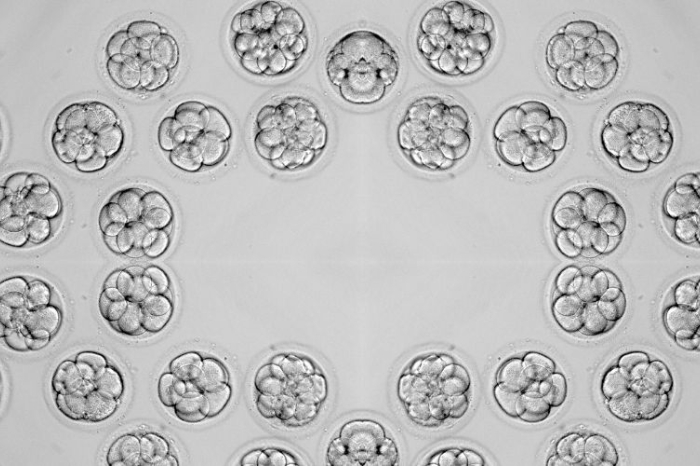

Allí, los biólogos revisan el contenido de cada folículo bajo el microscopio para identificar y separar los óvulos maduros. Este proceso dura entre 15 y 30 minutos, y tras unas horas de reposo en la clínica, la paciente puede regresar a casa el mismo día.

Es importante saber que no todos los folículos contienen óvulos y no todos los óvulos recuperados estarán maduros, lo que hace que la selección y el seguimiento médico sean fundamentales. Sin embargo, esta técnica permite reunir varios ovocitos en un solo ciclo y optimizar las posibilidades de éxito al fecundarlos en condiciones controladas. Después de la extracción, los óvulos se preparan para ser fecundados con los espermatozoides en el laboratorio, lo que da paso a la siguiente etapa del tratamiento: la formación de embriones.